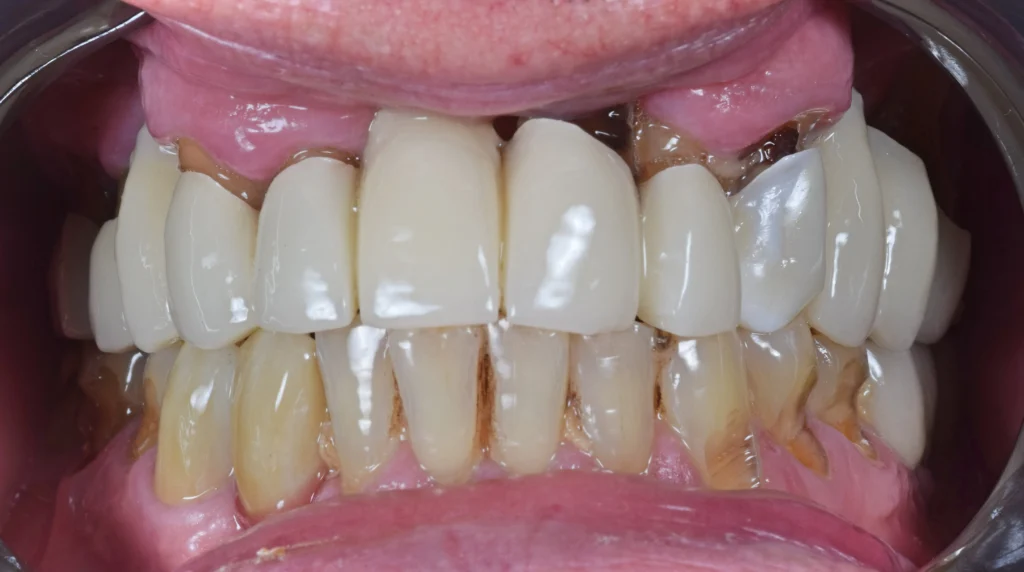

With a digital workflow we created a surgical guide, extracted all the teeth and immediately placed the dental implants using the surgical guide. The patient was provided with temporary teeth the next day.

After 5 months of healing the implants were integrated in the bone and we provided the patient with his final teeth. A hybrid construction with titanium and zirconia was made. A functional, healthy and natural smile was achieved.